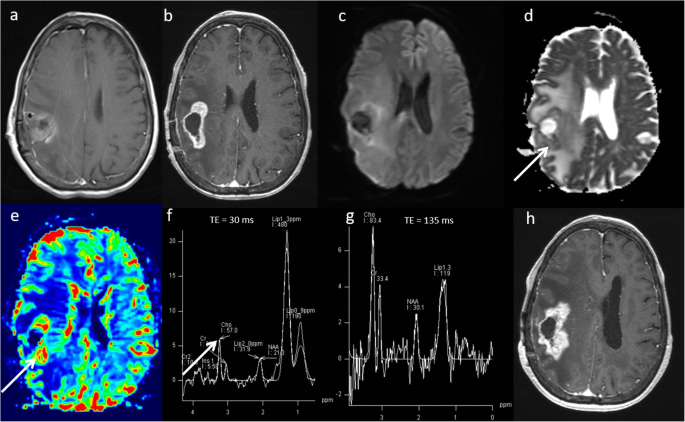

Glioblastoma—pseudoprogression. a Pre-operative T1-weighted image shows a right deep parietal region glioblastoma. b Conventional post-contrast T1-weighted image approximately 4 weeks after chemoradiotherapy treatment demonstrates a significant increase in the contrast-enhancing area (arrow). Multiparametric MRI at this timepoint demonstrates: c, d areas of high ADC (1186 × 10−6 mm2 s−1), (e) a low rCBV ratio (1.4, arrow) on PWI, (f, g) a low Cho/Cr ratio (1.4), a low Cho/NAA ratio and presence of lipid and lactate on MRS. Combination of parameters suggest pseudoprogression. h Clinical follow-up and conventional post-contrast T1W sequence at six months confirms a decrease in the amount of enhancing disease, indicating pseudoprogression

Glioblastoma—true progression. a Immediate post-operative contrast-enhanced T1-weighted scan following resection of a right fronto-parietal glioblastoma. b Conventional post-contrast T1-weighted image one month after chemoradiotherapy treatment demonstrates increase in the enhancing lesion size with associated oedema. Multiparametric MRI at this timepoint demonstrates: c, d areas of low ADC (903 × 10−6 mm2 s−1, arrow), (e) a high rCBV ratio (3.0, arrow) on PWI, (f, g) a high Cho/Cr ratio (2.3, arrow), high Cho/NAA ratio and presence of lipid/lactate on MRS. All parameters suggest a poor response and disease progression. h Six-month follow-up conventional post-contrast T1W sequence confirms an increase in enhancing disease, indicating true progression